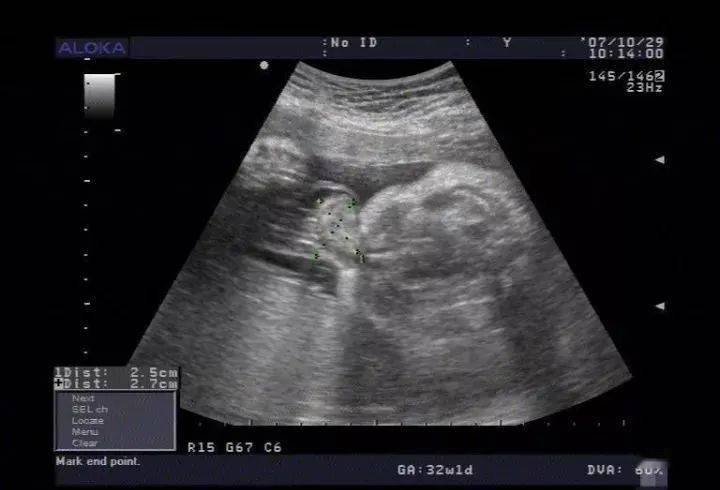

1.彩超的图像看起来还是黑白的,这正常吗?

这是正常现象

做了假彩超吧

2.正确答案:这是正常现象

3.答案解析:

彩超只有再看血管里面血流动方向的时候才表现为彩色,基本上屏幕全部都是黑白的,只有几个点是彩色的,所以并不是像彩色电视机那样全部都是彩色的,这是正常的。彩超检查可以清楚的发现一些疾病病变的位置以及病变情况,所以是一个重要的检查方法。